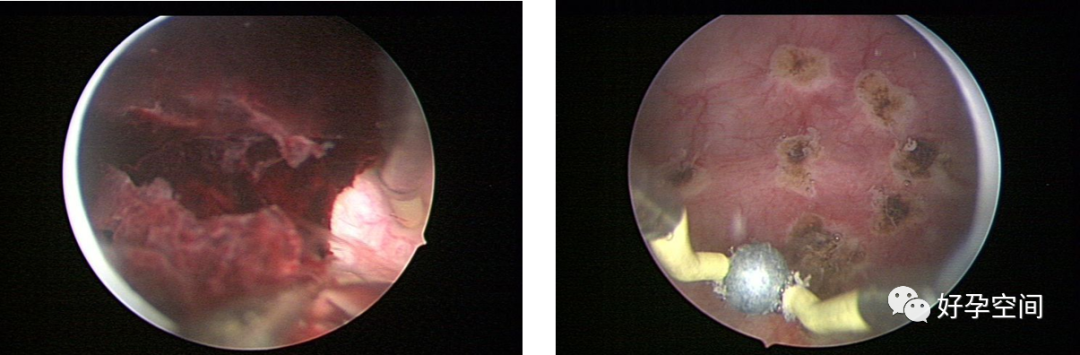

宫腔粘连,节育环嵌顿

胎盘残留、胎盘粘连、胎盘植入、动静脉瘘